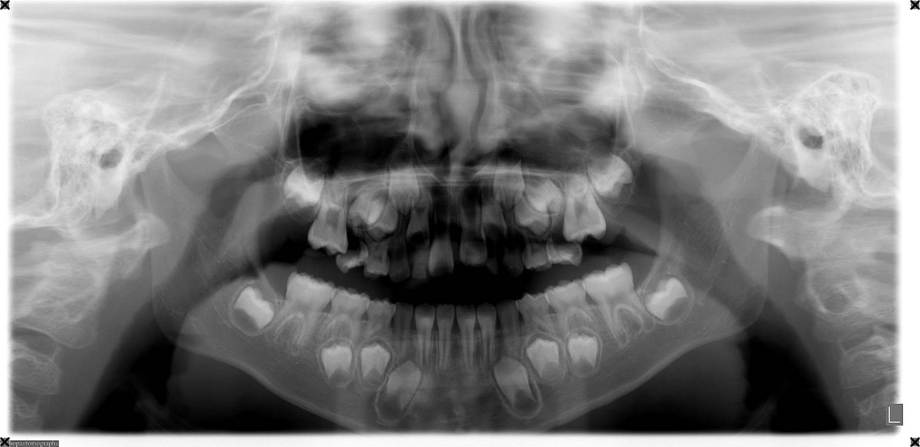

6歳9ヶ月の男の子。

上顎の第二乳臼歯が早期に脱落し後継永久歯の萌出スペースに明らかに不足しています。

ACCOという遠心移動床装置を使って2ヶ月でスペースを獲得しました。ACCOは家にいるときだけ使用してもらいスペースの維持をして経過観察を行っています。

治療費:¥435,000(税別) ACCOによる遠心移動の治療期間:2ヶ月

副作用・リスク:ACCOの使用を怠ると後戻りすることがある